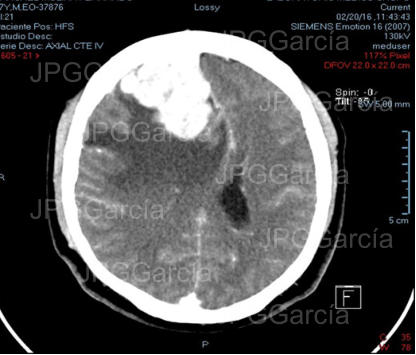

Resultado de tomografía craneal postquirúrgica en donde se observa drenaje del absceso cerebral